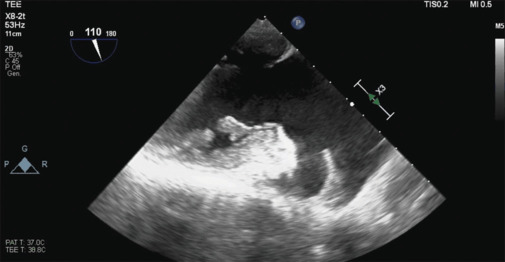

Papillary muscle rupture (PMR) is a cardiac surgical emergency, and early treatment is associated with better short- and long-term survival outcomes. The sensitivity of the transthoracic echocardiogram for PMR is rather low (65%), and in acute, the diagnosis could be difficult given the clinical, laboratory, and radiological aspects not specific for the disease. We report a case of incomplete anterolateral PMR in a patient admitted to intensive care with bilateral pneumonia and septic shock. Transesophageal echocardiogram was fundamental for a better visualization of mitral subvalvular apparatus, allowing a correct diagnosis and a tempestive treatment.

乳头状肌破裂(PMR)是一种心脏外科急诊,早期治疗与较好的短期和长期生存结果相关。经胸超声心动图对PMR的敏感性相当低(65%),在急性期,由于临床、实验室和放射学方面的原因,诊断可能很困难。我们报告一例不完全前外侧PMR患者入院重症监护双侧肺炎和感染性休克。经食管超声心动图是更好地显示二尖瓣下器官的基础,允许正确的诊断和快速治疗。